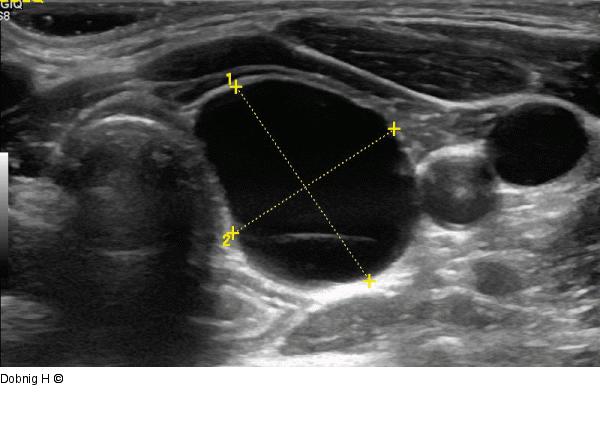

Abbildung 6: Alkoholablation - Schilddrüse Gleiche Zyste wie in Abbildung 5. Horizontalebene. |

Gleiche Zyste wie in Abbildung 5. Horizontalebene. |